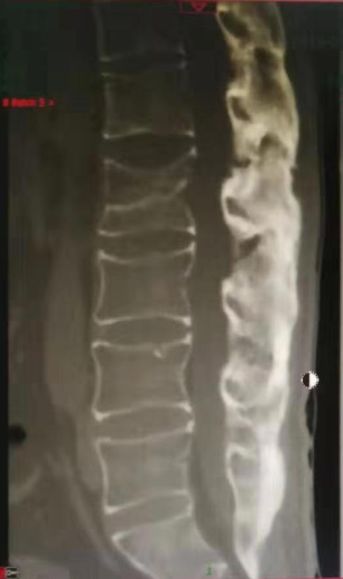

腰椎MRI及CT显示腰1 腰2椎体新鲜压缩骨折

术后复查见腰1、腰2椎体高度恢复,螺钉位置满意